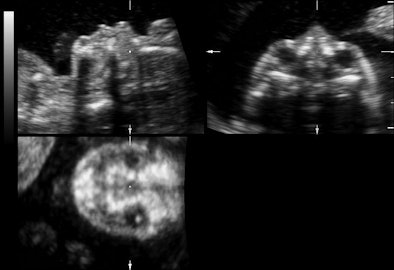

![]() |

| Representative fetal profile images showing good-quality (above), acceptable-quality (below), and poor-quality (bottom) images. All images courtesy of the Journal of Ultrasound in Medicine. |